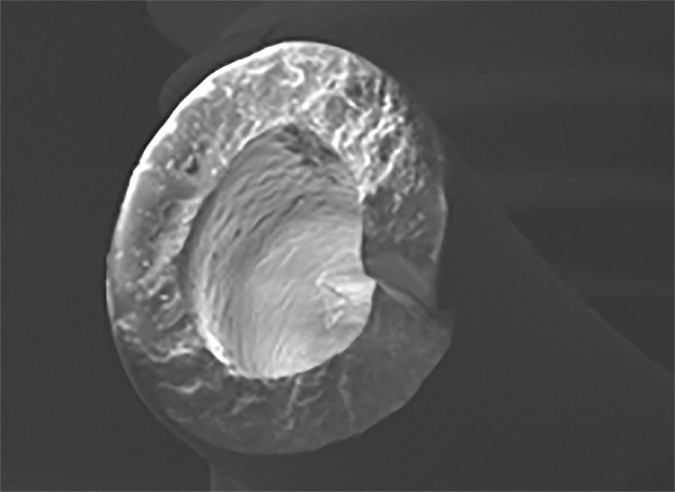

A, Overview (×100) of catheter at site of rupture.

Braun et al. [4] performed a set of experiments investigating the mechanical properties of both de novo and explanted port catheters. They found clear correlation between material properties and clinical performance. Specifically, both native catheters exposed to moderate mechanical stress tests and explanted catheters from cancer patients had a progressive loss of barium sul-fate (BaSO4) particles, which are introduced in almost every catheter material to make it radiopaque. The loss of BaSO4 particles between the silicon bonds essentially leaves microscopic holes in the catheter, leaving areas of increased vulnerability that render the catheter prone to rupture (Fig. 1). Interestingly, more BaSO4-related cracks were observed in silicone than in polyurethane catheters.